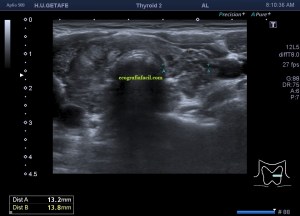

Era un nódulo hiperecogénico en el contexto de la tiroiditis en el estudio de una ecografía tiroidea.

Te enseño las imágenes, típicas de una exploración tiroidea de protocolo con semiología de tiroiditis.

Mira las imágenes y luego te explico un poco, poco, porque no tiene mucho que explicar…

De la imagen 1 a 7 el protocolo habitual, el estudio particular del nódulo con medidas y aplicación del doppler demuestra el aspecto típico del Caballero Blanco.

La imagen 12 y 13 están adquiridas con una sonda de 18 Mhz.

Resumen de las imágenes que has visto en el caso de hoy:

1. Hipoecogenicidad del parénquima

2. Heteroecogenicidad

3. Múltiples nódulos hipoecoicos muy pequeños

4. Doppler Color y Doppler Power aumentado de tamaño en el nódulo

Este es el aspecto ecográfico descrito anteriormente de la patología que habitualmente puede albergar el nódulo del que trata hoy el post y que no es otra que la de la Tiroiditis de Hashimoto.

El Caballero blanco, recibe el nombre debido a su semiología hiperecogénica, homogénea y solitaria circunscrito en la patología referida con anterioridad, puede aparecer en esta patología de forma benigna o degenerar en otro tipo de patología a formas malignas como el linfoma tiroideo.